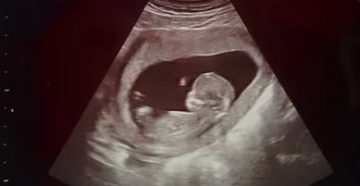

Как расшифровать УЗИ на 12 неделе беременности? Период беременности очень важный период для беременной женщины…